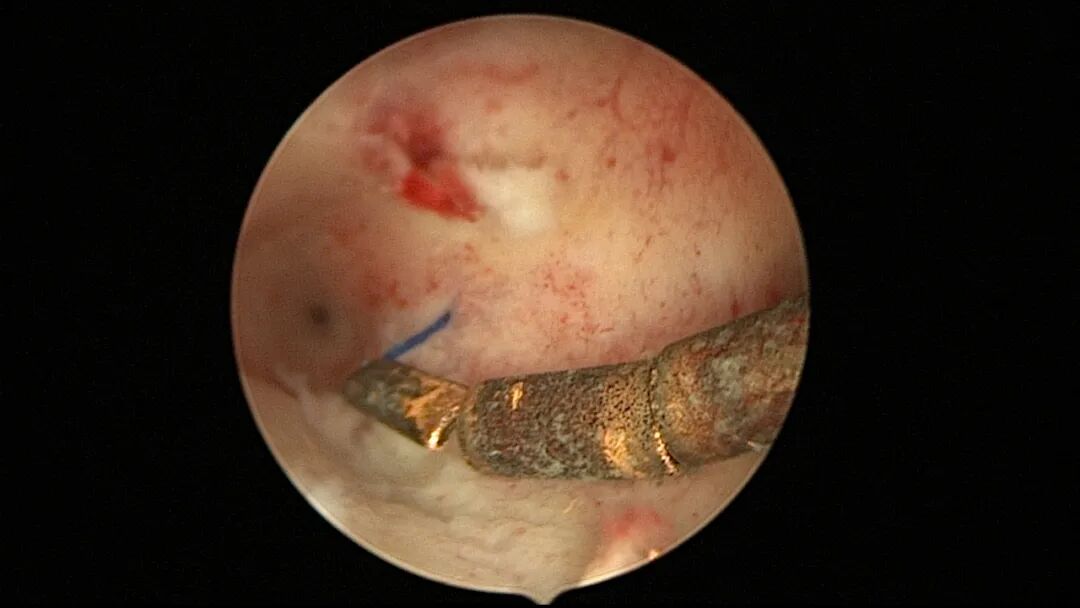

自制不锈钢挂钩,材料选择:麻醉包硬膜外导管内钢丝,较细较软,插入宫底肌层没问题,碰到宫颈组织容易弯曲。中医针灸钢针,更有韧性,是我们的主要选择。挂钩制作:1把剪刀、2把止血钳即可完成挂钩制作。剪切1.5cm~2cm钢丝可以做成1cm~1.2cm长挂钩。倒钩端短一点,约占挂钩全长的三分之一,倒钩尖端弯曲钢丝不夹拢,减少倒钩断裂机会。挂钩处钢丝留一小缝隙,不可以交叉,便于节育环固定线圈滑过挂钩挂上。挂钩消毒:碘伏浸泡消毒,或酒精燃烧灭菌。

挂钩制作材料图片

操作步骤描述:宫腔检查镜可完成操作,扩张宫颈至7号扩宫棒,检查镜能轻松通过,避免镜鞘与节育环纵臂在宫颈管形成卡压及筷子效应,影响操作,或卡压摩擦阻力大带出节育环。可用单级电针在宫底扎出小凹坑做标记或作为置入挂钩的隧道(不是必须的)。将挂钩用异物钳直视下送入宫腔,或用中弯钳盲视下送入宫腔,异物钳夹持挂钩将倒钩端插入宫底肌层,越过倒钩。用环尾丝或不可吸收线在节育环顶端打结,形成一个线圈,直径约0.5cm~1cm,结打在线圈旁边,便于夹持操作。将环装回推杆送入宫腔,再夹住节育环固定线圈抵紧宫壁稍旋转就可以将线圈滑进挂钩缺口,挂到挂钩上,可再次向宫底推送挂钩少许,不必夹闭挂钩缺口,重力作用和内膜生长都会阻止线圈脱出,可以用电针电凝挂钩周围组织,进一步防止挂钩脱落。异物钳原位固定节育环,退出宫腔镜,距宫颈外口0.5cm~1cm剪断剩余尾丝。宫颈扩张到9号扩宫棒,冷刀系统异物钳夹持挂钩及线圈也可完成以上操作。

挂钩固定注意事项:月经干净3~7天手术,此时内膜最薄,利于挂钩固定到子宫肌层,如果内膜较厚,最好用负压吸引器去除内膜,暴露基底层,挂钩才能放置到位,也避免内膜掀起、出血等影响操作。挂钩尖端能轻松在子宫壁上粘附,然后调整钳的位置,将挂钩插入到宫底肌层。也可以在体外连接好挂钩和节育环,同时送入宫腔,异物钳在宫腔夹持挂钩并插入宫底肌层。术后复查B超节育环距宫底距离可能较大,个别达3cm左右,跟子宫大、宫壁厚、外加挂钩长度及线圈长度之和较大有关,保持这个距离不再延长即为手术成功。